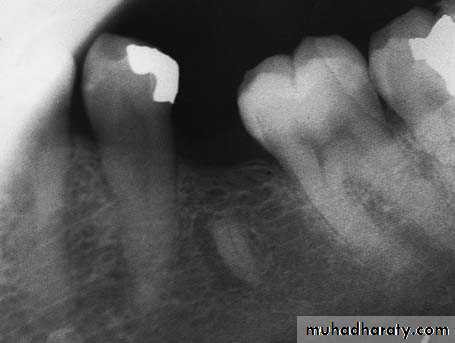

1- a mandibular molar with hypercementosis at the distal root tip.

2- Envelope flap is reflected, part of the buccal plate is removed, and the tooth is sectioned buccolingually at the crown as far as the intraradicular bone3- Extraction of the normal part of the root then widening of the alveolus with a round bur, so that removal of the root is possible without fracturing the bulbous root tip. Extraction of the distal portion of the tooth using forceps after creating a pathway for removal